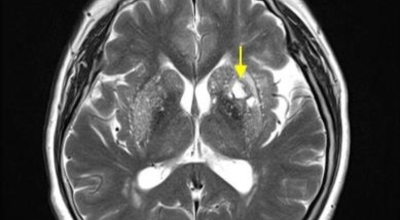

뇌조직은 평소에도 다량의 혈류를 공급받고 있는데 어떤 여러가지 원인으로 인해서 뇌혈관에 이루는 관이 막히는 경우 뇌에 공급되는 혈액량이 떨어지면서 뇌조직이 기능을 제대로 하지 못하게 되는데 이렇게 뇌혈류 감소가 일정 시간 이상 지속되다 보면 뇌조직의 괴사가 시작되어 회복 불가능한 상태가 되는데 이를 뇌경색이라 해요. 오늘 알아볼 질병은 뇌경색 초기증상이예요.

뇌경색의 경색이란 허혈성 괴사를 말해요. 여기서 허혈이란 혈관이 막히는 것을 말하고 괴사는 말 그대로 일부가 죽는 것을 말하는데 뇌경색의 경우 뇌의 혈관이 막혀 뇌세포 일부가 죽는 걸 의미해요. 뇌혈관이 막혔다 해서 혈액 공급이 안되는것은 또 아니에요.